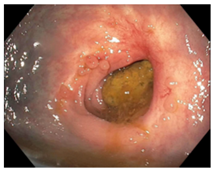

| Endoscopy | Flat white scar Telangiectasia Absence of ulcers and mucosal nodularity | Small mucosal nodules/minor mucosal irregularities Superficial ulceration Mild, persistent erythema of the scar | Visible tumor |

| Flat, white scar | ![]() | ![]() | ![]() |